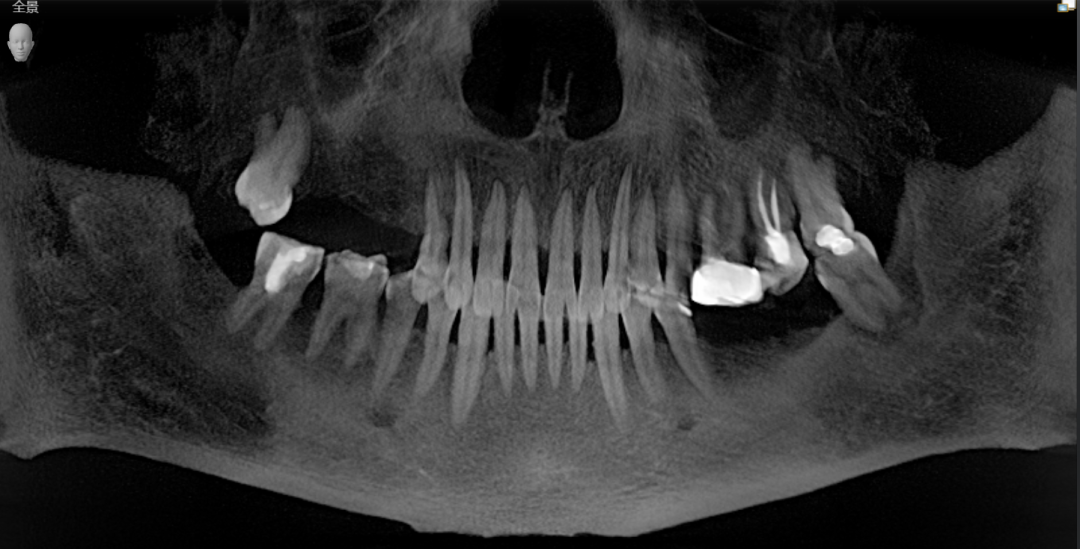

叔叔术前口内CBCT全景照

看到阿姨总是忽视自己,对自己的身体健康蛮不在乎的样子,叔叔也非常焦心。就先在海德堡联合口腔做了种植牙手术,做了4颗种植体。

曹申主任为阿姨进行了数字化的会诊,借助Sirona CBCT全景影像信息和相关修复信息为基础,借助数字化专业种植设计软件进行术前诊断和种植方案规划。